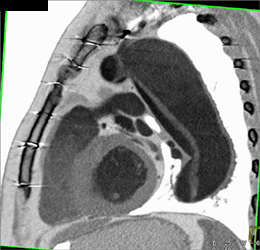

Diagnosis

Tracheal Bronchu